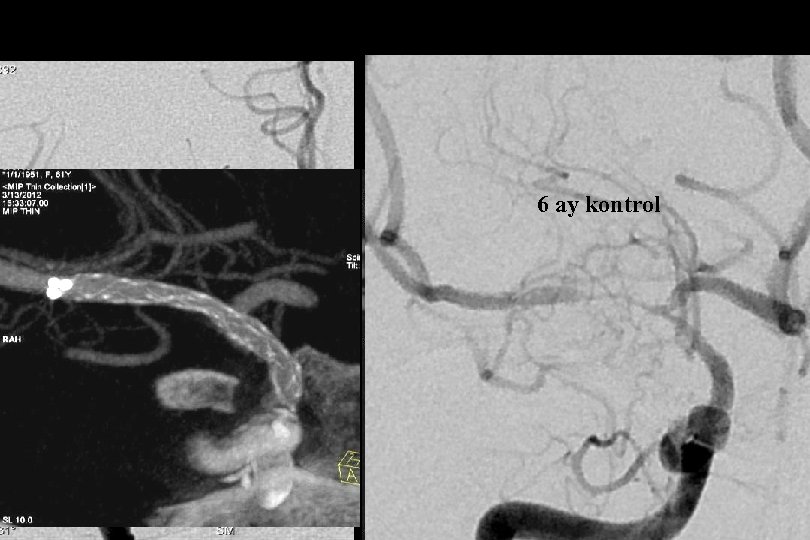

6 ay kontrol

52 y kadın efektiv/test edilmiş ikili antiagregan ted altında iken multipl TIA Basit PTA sonrası

1. Yıl kontrol

1 yıl kontrol PTA Sonrası